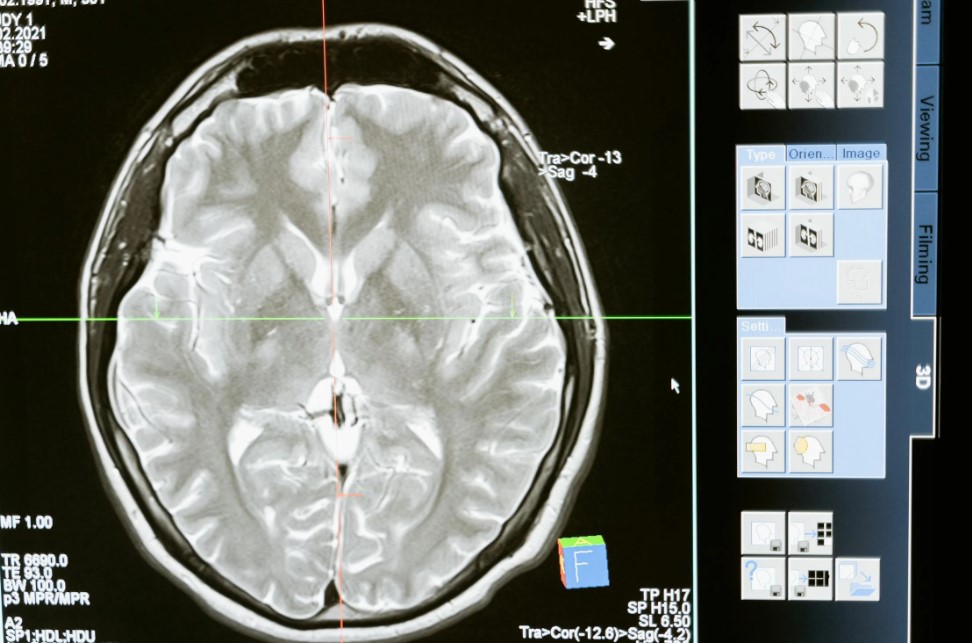

For example, after a serious accident, a patient with traumatic brain injury could be brought to hospital and undergo detailed brain imaging. Based on this scan, clinicians could inject magnetoelectric nanoparticles directly into the affected regions, in quantities tailored to the individual patient.

“These decisions could be guided by personalised computational models of the brain,” said Parazzini.